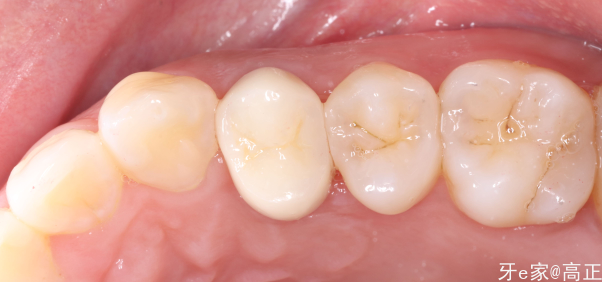

聚合瓷全冠

需要注意的是调整侧方咬合,尽量减轻4号牙的侧方合接触